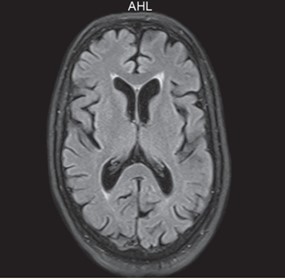

Como se evidencia en la imagen anterior, los opioides producen daños estructurales en el SNC, como la atrofia cerebral, que a su vez tiene una asociación con la edad y la duración de la adicción. Conviene mencionar una investigación retrospectiva que empleó 40 pacientes con abuso de opioides, con el propósito de evaluar la asociación entre el abuso crónico de estas drogas y la atrofia cerebral, utilizando los estudios radiológicos de los pacientes. Los casos se evaluaron durante dos años y se incluyeron pacientes ingresados en Unidad de Cuidados Intensivos (UCI).(1)

En el estudio indicado, se encontró que la mayoría de los consumidores (35%) tenía una edad que oscilaba entre los 36 y 40 años. Los 40 pacientes incluidos en el estudio eran adictos crónicos de opiáceos, de los cuales 25 tenían atrofia cerebral de leve a grave. De estos, 25 sujetos (62,5%) mostraron evidencia radiológica de atrofia cerebral, mientras que los 15 restantes no tenían signos que sugirieran atrofia cerebral. Entre los que tenían atrofia cerebral, 14 presentaban de grado I, 7 tenían atrofia cerebral de grado II, III y IV(1) (ver Imágenes 20 y 21).